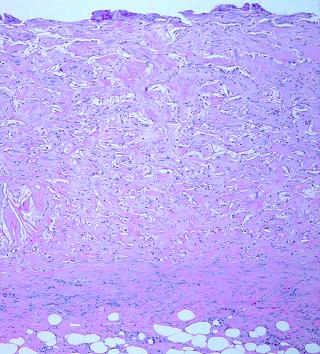

21 - Maturation.  Normal inflammatory wound healing follows a pattern of “overshoot-then-involute”.  The acute inflammatory repair phase is rapid, aggressive, and open loop.  Instead of the wound creating a model of normal tissue, it “overshoots”, quickly resulting in an excessive density and quantity of new blood vessels and immature connective proteins.  These early events are measured in days to weeks.  Once the wound is epithelialized and proliferation ceases, the scar undergoes a maturation process in which excessive elements of repair involute.  Erythema fades, scar becomes more compliant, and scar histology gradually transforms back toward normal dermis.  Scar maturation is measured in months and years, and in the interval, scar complications can cause all manner of troubles.  Integra does not have this overshoot-involute pattern.  Instead, Integra undergoes an orderly targeted evolution which leads to a dermal analogue without any oscillatory behavior.  Regenerated Integra is a nearly mature, mechanically compliant, esthetically acceptable tissue by the time that skin grafts are healed.  This behavior is a consequence of closed loop controls on cell migration and proliferation which are typical of both Integra and embryonic histogenesis.  Integra histogenesis is measured in weeks to months, in a middle zone between inflammatory repair and scar maturation.  The matrix itself disappears slowly by passive hydrolysis, preserving much of its original architecture for as long as four years.  (figure 14).

Figure 13   (left)

This is Integra one year after placement.  As time goes by, normal physiological remodeling of dermal collagen causes the neodermis to slowly look more like natural dermis.  That process is evident here, seen as the formation of discrete separated wavy collagen bundles, many of them transverse and parallel, typical of native dermis.  However, most of the matrix still persists, and whatever collagen remodeling is taking place, it continues to respect the boundaries imposed by the matrix.  The neodermis conforms to the matrix, rather than distorting the matrix the way that contracting scar distorts anything in its way.

Figure 14   (right)

(a, top left)  Normal reticular dermis.  Large, parallel, mostly transverse collagen bundles are separated by interstitial spaces.  Typical fibroblasts in typical densities are dispersed throughout

(b, top right)  Normal reticular dermis from another subject.  There is variability in the size and orientation of dermal collagen from specimen to specimen, due to location, skin thickness, local biomechanics, orientation of the specimen cuts relative to local skin anisotropies (Langer’s lines, fibers seen parallel or on end), and intersubject variability.  Thus the two top specimens look different, but both are normal reticular dermis.  Collagen bundles are large, somewhat coiled, wavy, or springy.  They are largely individualized and distinct, separated by interstitial spaces.  These factors permit elastic compliance of the material, and normal motion of related body parts

(e, bottom left)  Matured scar.  This scar, at 2 years old, is still cellular compared to normal dermis, but not by much.  The scar collagen has undergone a gradual transformation.  It is now bundled and springy, looking mostly like normal dermis.

(f, bottom right)  Old Integra at 4 years.  The original matrix is largely gone in this area (but it is still abundant in some other out-of-view areas of this biopsy).  For septae that do remain, their morphology is still unaltered.  Just as with scar, normal physiological collagen remodeling is also slowly making this specimen look like normal dermis.  However, in sharp contrast to scar, Integra has, from the outset, a structure and properties that are already very close to dermis, thereby avoiding scar complications.